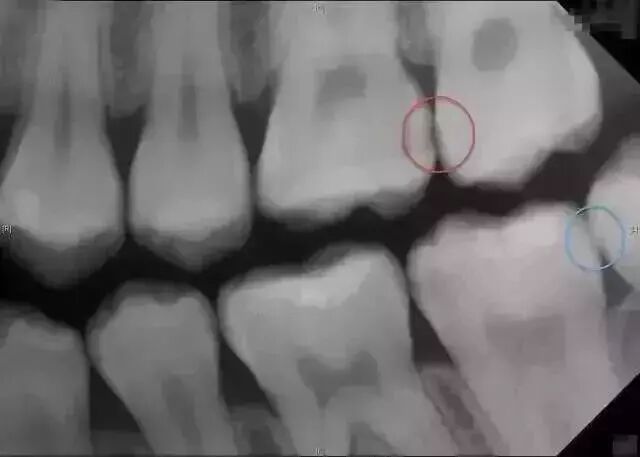

透過呢啲片可以了解齒嘅病變情況X光片除了了解牙齿病变情况,

還可以了解牙槽骨內是否有埋伏牙、多生牙、牙齒有冇空洞、牙根底下有冇包囊、周圍骨頭有冇吸收等,

憑據X線片綜合分析可以提高醫生診斷治療牙齒嘅準確性同成功率。

所以,除咗外層啲牙釉質,牙齒裏面出咗問題,單憑肉眼根本睇唔到。

友情提示:拔智齒、做根管治療、補牙、牙周病、种植牙、牙齒矯正等都需要進行拍片。